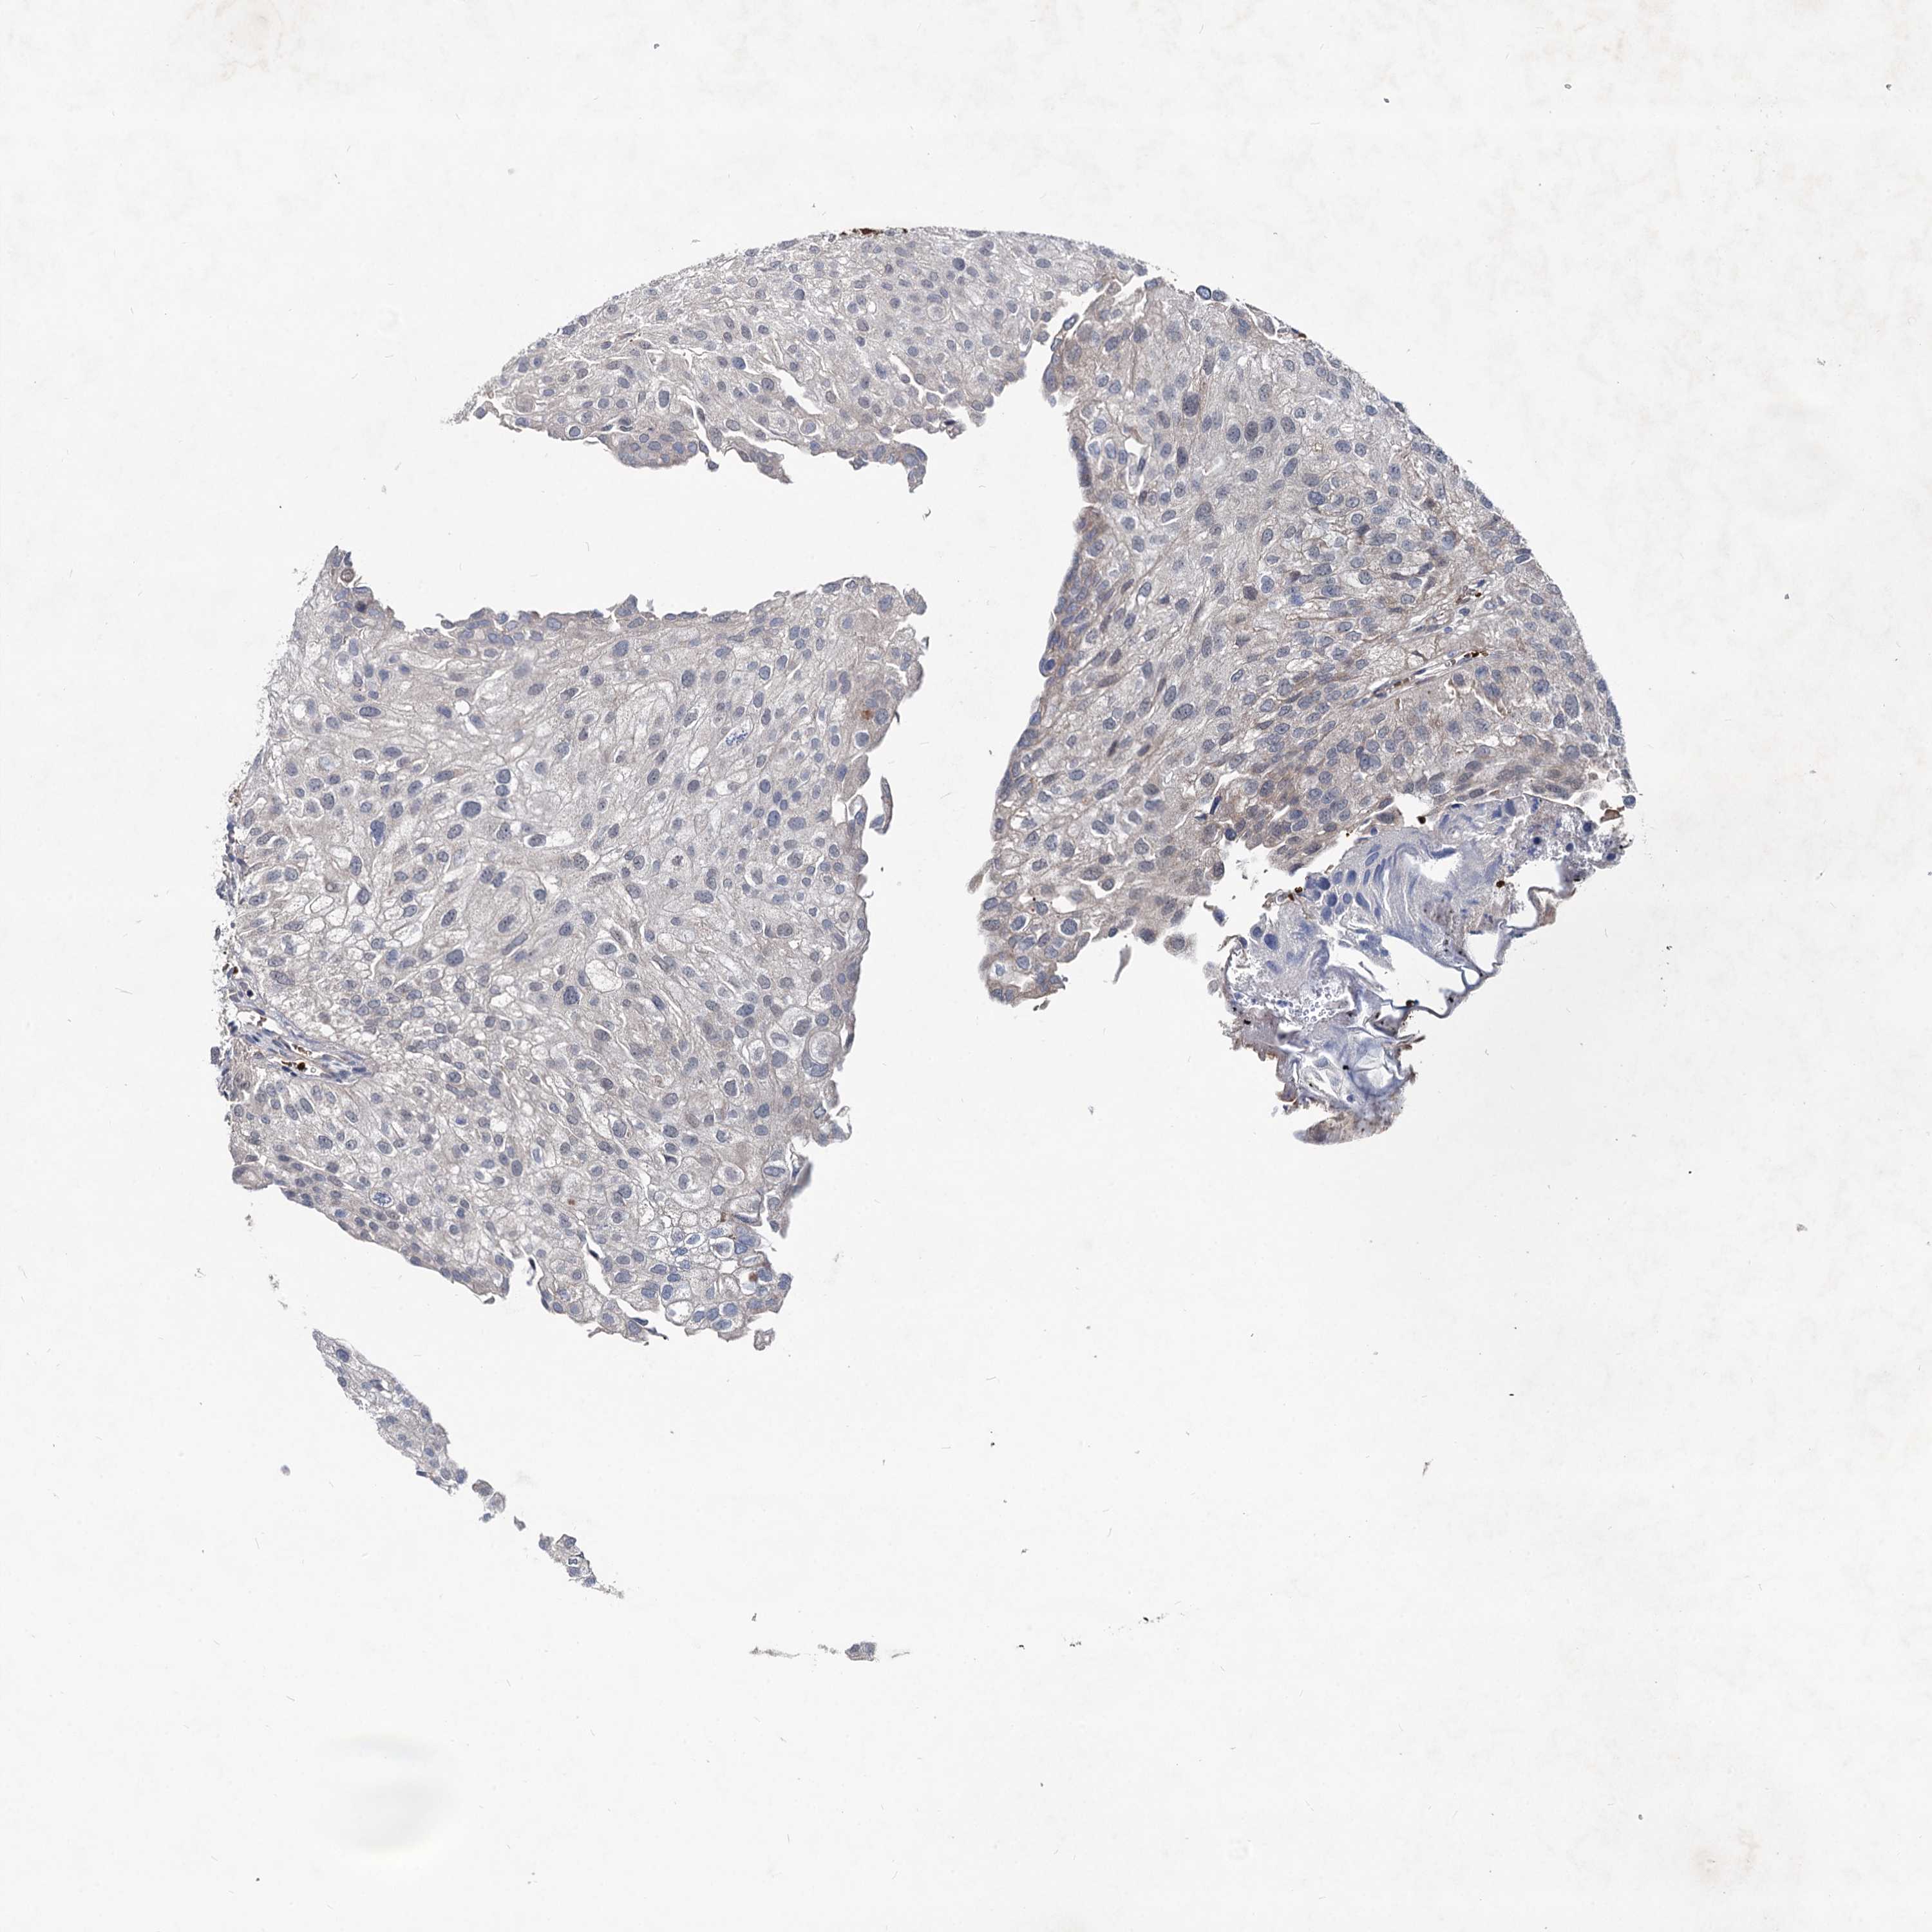

UROTHELIAL CANCER - Protein expressioni

A mouse-over function shows sample information and annotation data. Click on an image to view it in a full screen mode. Samples can be filtered based on level of antibody staining by selecting one or several of the following categories: high, medium, low and not detected. The assay and annotation is described here.

Note that samples used for immunohistochemistry by the Human Protein Atlas do not correspond to samples in the TCGA dataset.

Antibody stainingi

Antibody staining in the annotated cell types in the current human tissue is reported as not detected, low, medium, or high, based on conventional immunohistochemistry profiling in selected tissues. This score is based on the combination of the staining intensity and fraction of stained cells.

Each image is clickable and will lead to virtual microscopy that enables deeper exploration of all samples and also displays staining intensity scores, fraction scores and subcellular localization as well as patient and tissue information for each sample.

Antibody HPA039343

Antibody HPA040048

Urothelial carcinoma, High grade

Urothelial carcinoma, Low grade